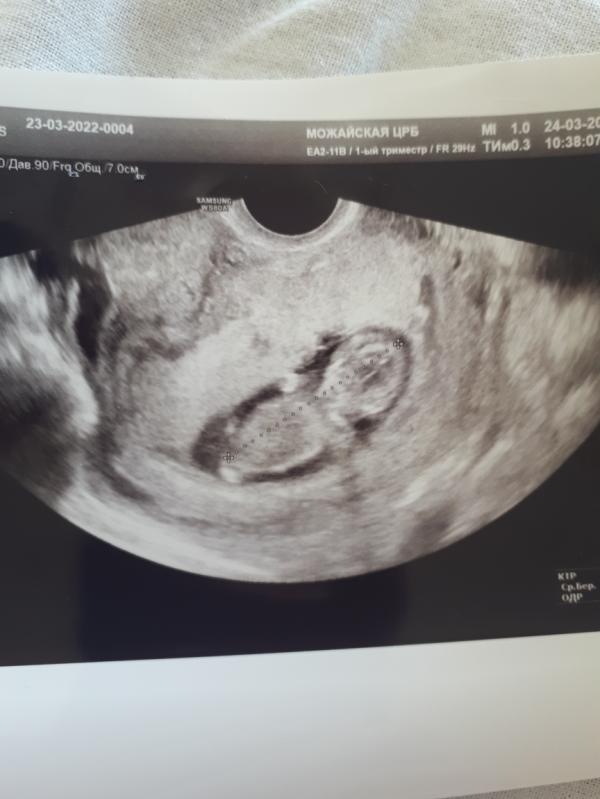

Срок на снимке УЗИ 11,4 недель, врач сказала всё хорошо, а Я никак не пойму, почему у кого то на моём сроке, места вокруг ребенка много, а у меня, как будто он в тисках. Ну и если кто то умеет определять, предположите, я надеюсь мальчик🎩

стенки как будто давят на малыша. врач мне показывала и объяснила, что это тонус. во время узи бывает!

@sergeeva_olya Я пока не была ещё у врача с момента УЗИ. Узист ничего не сказал на этот счёт. А я просто дома нашла старый снимок УЗИ сына на этом сроке, просто хотела сравнить, и увидела там ооочень много места. Вот и закралась мысль...

Мне кажется у вас ракурс узи такой )))) но вообще необычно смотрится, согласна😁